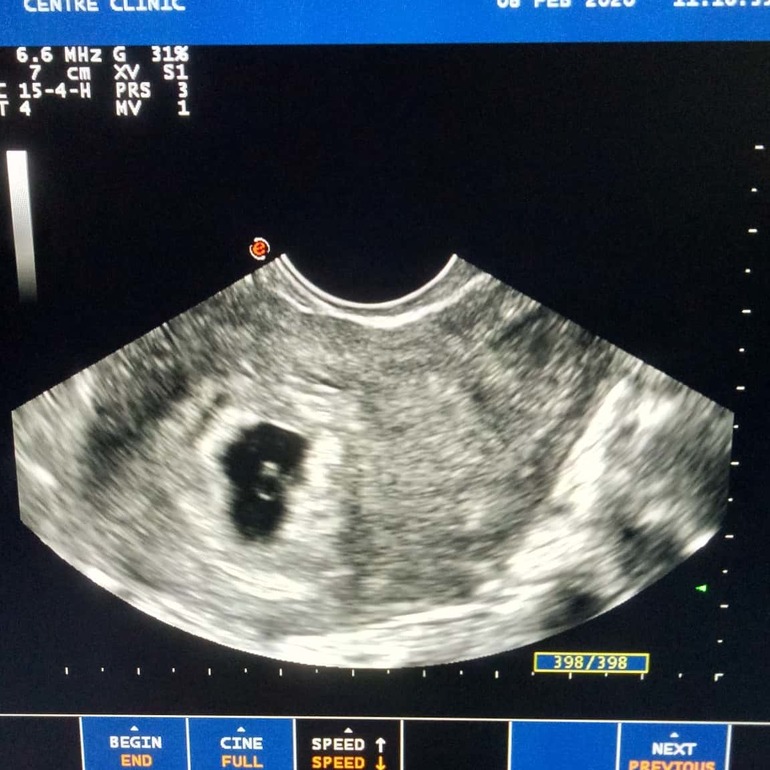

УЗИ. Большое плодное яйцо. Прокомментируйте, пожалуйста.

Первое УЗИ, срок по М 6+1. Ре считает ровно 5 недель, так как цикл длинный. Плодное яйцо большое уже. В левом яичнике 2 ЖТ, просто не захотели подсвечивать.